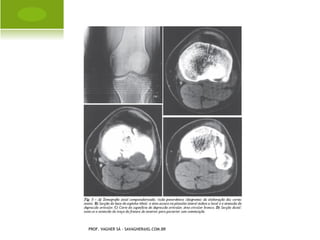

   Radiograficamente, são lesões predominantemente osteolíticas,

destrutivas, bordas indistintas, com lesão da cortical, ruptura do

periósteo e invasão de partes moles.

   A localização mais comum do osteossarcoma é na metáfise

superior da tíbia e úmero e na metáfise inferior do fêmur e rádio,

com predomínio ao redor do joelho.

PROF. VAGNER SÁ - SAVAGNER@IG.COM.BR

OSTEOSSARCOMA